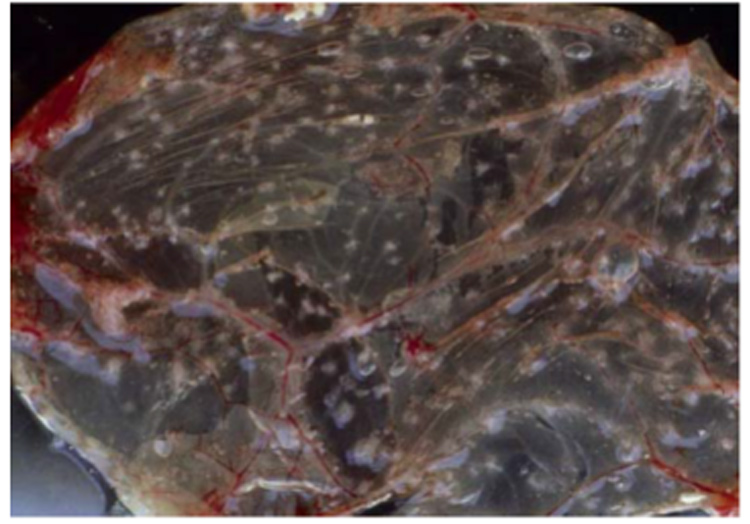

常用的病毒分離方法是將病料接種于雞胚的絨毛尿囊膜。傳喉病毒會在此處形成不透明的斑塊(圖4)。病毒分離相對于PCR成本更高,耗時更長,對采樣和送樣的要求也更高。但是通過病毒分離可以獲得活病毒,以便于做進一步的毒力和組織嗜性等方面的研究。PCR和病毒分離都存在一個相同的缺陷,即只能證明傳喉病毒在病雞體內(nèi)存在,但是不能直接證明是傳喉病毒導致了雞發(fā)病。

圖4:雞胚絨毛尿囊膜上的斑塊(來源:LDA 22)